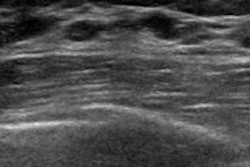

Breast ultrasound is an important tool in the detection of breast masses. While studies have shown that the technique can consistently detect additional cancers when used as a supplemental screening modality, it is prone to false positives and has lower sensitivity compared with breast MRI.

The NYU team trained its AI model using its large-scale, institutional dataset of 345,370 breast ultrasound exams acquired from 168,282 patients between 2012 and 2019.

The team then tested the algorithm alongside 13 human imaging readers with varied expertise. Each reader reviewed 250 breast ultrasound exams that were randomly sampled from the test set. A hybrid decision-making model was then created for each reader, which made predictions by evenly weighting the predictions of the reader and the AI system.

Among the exams included in the study, 392 breasts were imaged, 38 of which had malignant lesions.

The AI model achieved an area under the receiver operating characteristic (AUC) of 0.880, significantly outperforming each of the 13 readers (p < 0.01). The performances of the human readers achieved 0.818 AUC on average, none of which exceeded the AI model's performance.

However, the accuracy of the readers improved with the help of AI. The hybrid predictions of each reader and the AI algorithm improved the average diagnostic accuracy for all readers, including attending radiologists and trainees, to 0.852 AUC (p < 0.01).

| Accuracy of breast ultrasound with and without AI assistance | ||

| Average AUC without AI assistance | Average AUC with AI assistance | |

| Radiologists | 0.824 | 0.863 |

| Trainees | 0.805 | 0.826 |